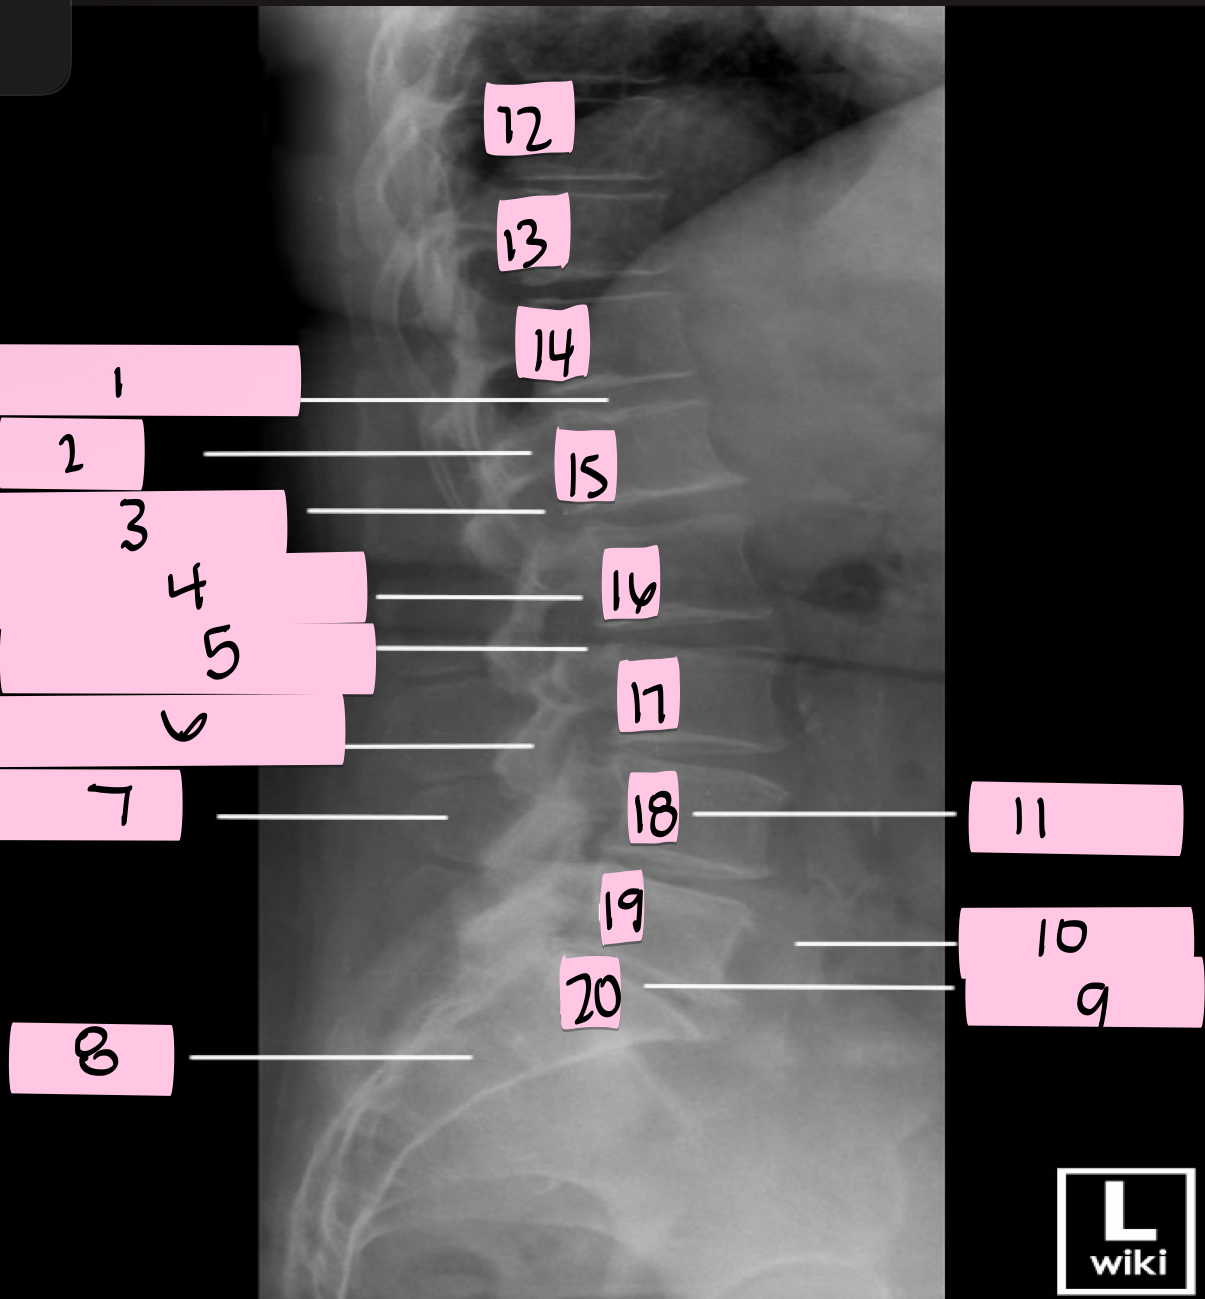

What is 1 pointing to?

Intervertebral disk

What is 2 pointing to?

Pedicle

What is 3 pointing to?

Intervertebral foramen

What is 4 pointing to?

Inferior vertebral notch

What is 5 pointing to?

Superior vertebral notch

What is 6 pointing to?

Inferior articular process

What is 7 pointing to?

Spinous process

What is 8 pointing to?

Sacrum

What is 9 pointing to?

L5 S1 joint

What is 10 pointing to?

Iliac crest

What is 11 pointing to?

Vertebral body (L4)

What is 12 pointing to?

T10

What is 13 pointing to?

T11

What is 14 pointing to?

T12

What is 15 pointing to?

L1

What is 16 pointing to?

L2

What is 17 pointing to?

L3

What is 18 pointing to?

L4

What is 19 pointing to?

L5

What is 20 pointing to?

S1